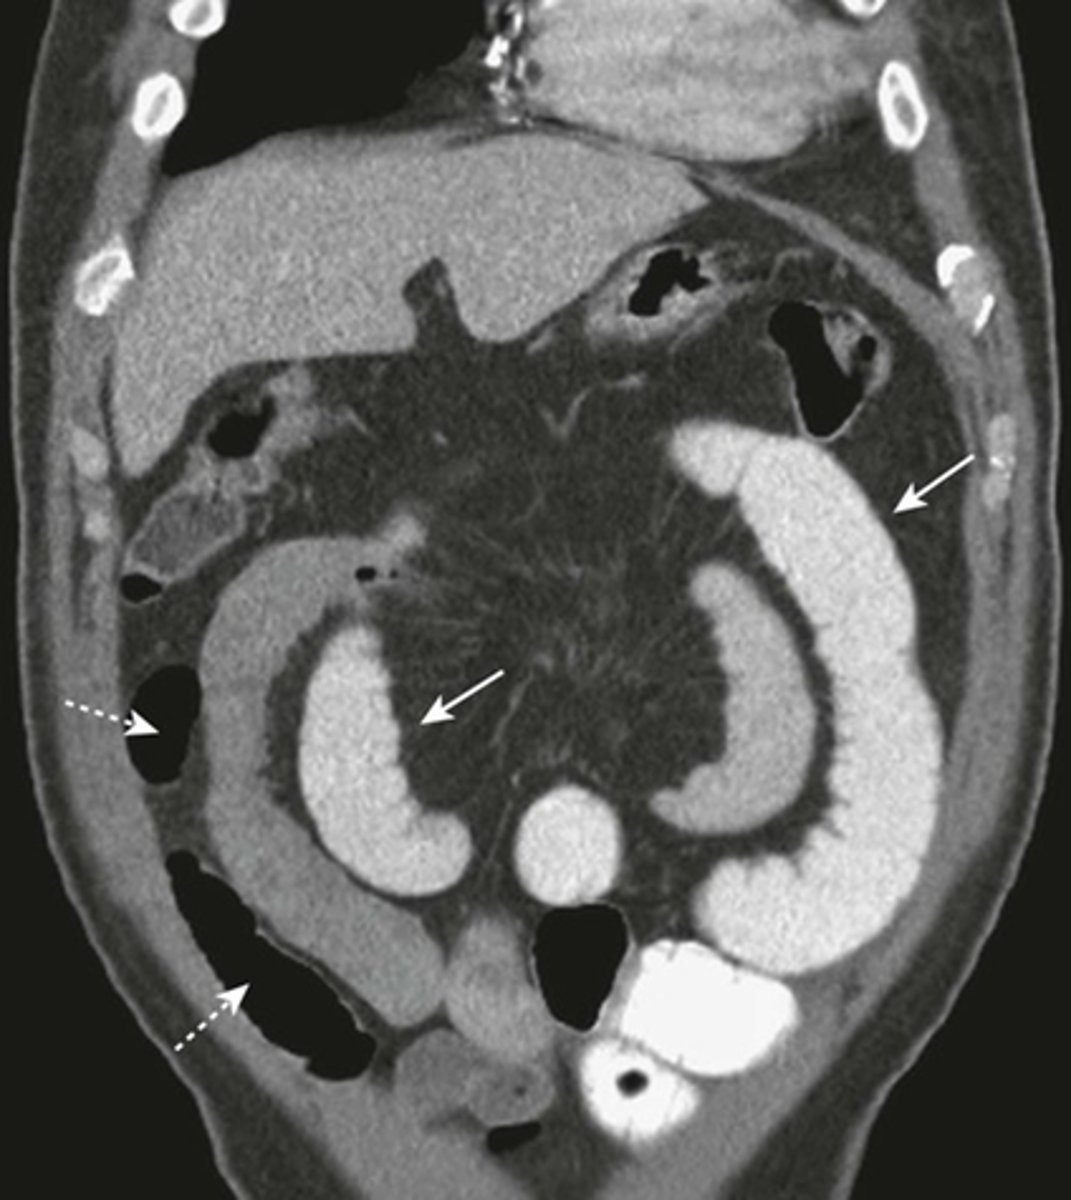

CT with IV contrast of SBO.

SOLID BLACK ARROWS: multiple fluid- and contrast filled dilated loops of small bowels.

WHITE ARROWS: Collapsed colon

DOTTED BLACK ARROW: Right renal cyst